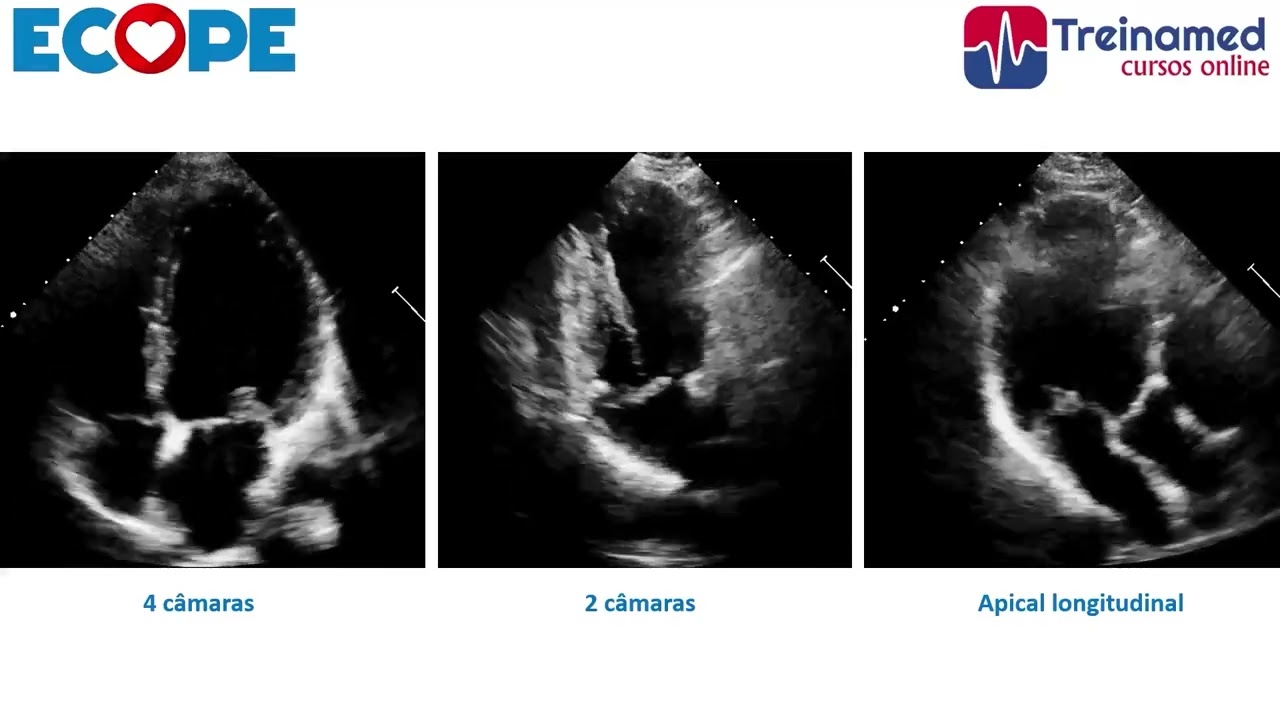

Vamos aprender a estudar a valva mitral a partir do modo unidimensional (modo-M). É muito importante o cardiologista aprender a olhar para as imagens que são disponibilizadas no exame de Ecocardiograma.

PLANOS ECOCARDIOGRÁFICOS